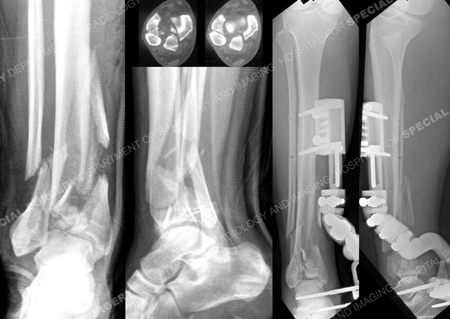

Anteroposterior (AP) and lateral x-rays reveal an AO/OTA Type 43-C3 distal tibia pilon fracture with extensive articular involvement; (right images) AP and lateral x-rays of the right ankle following placement of a spanning external fixator;

(top images) CT scan images delineating the articular fracture lines.